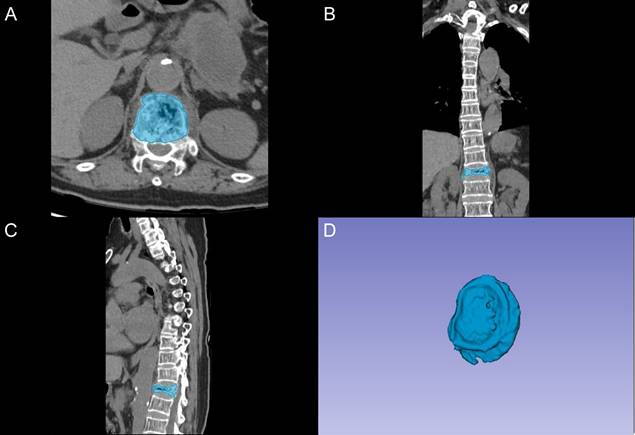

Comparison of Artificial Intelligence Models Using CT Radiomics for Predicting Post-Vertebral Augmentation Residual Back Pain in Osteoporotic Vertebral Compression Fractures Chen Ge, Changwei Li, Yaoqing Zhu, Chonglin Yang, Xiangyang Xu Int. J. Med. Sci. 2025; 22(13): 3329-3341. doi:10.7150/ijms.114419 Full text PDF PubMed PMC